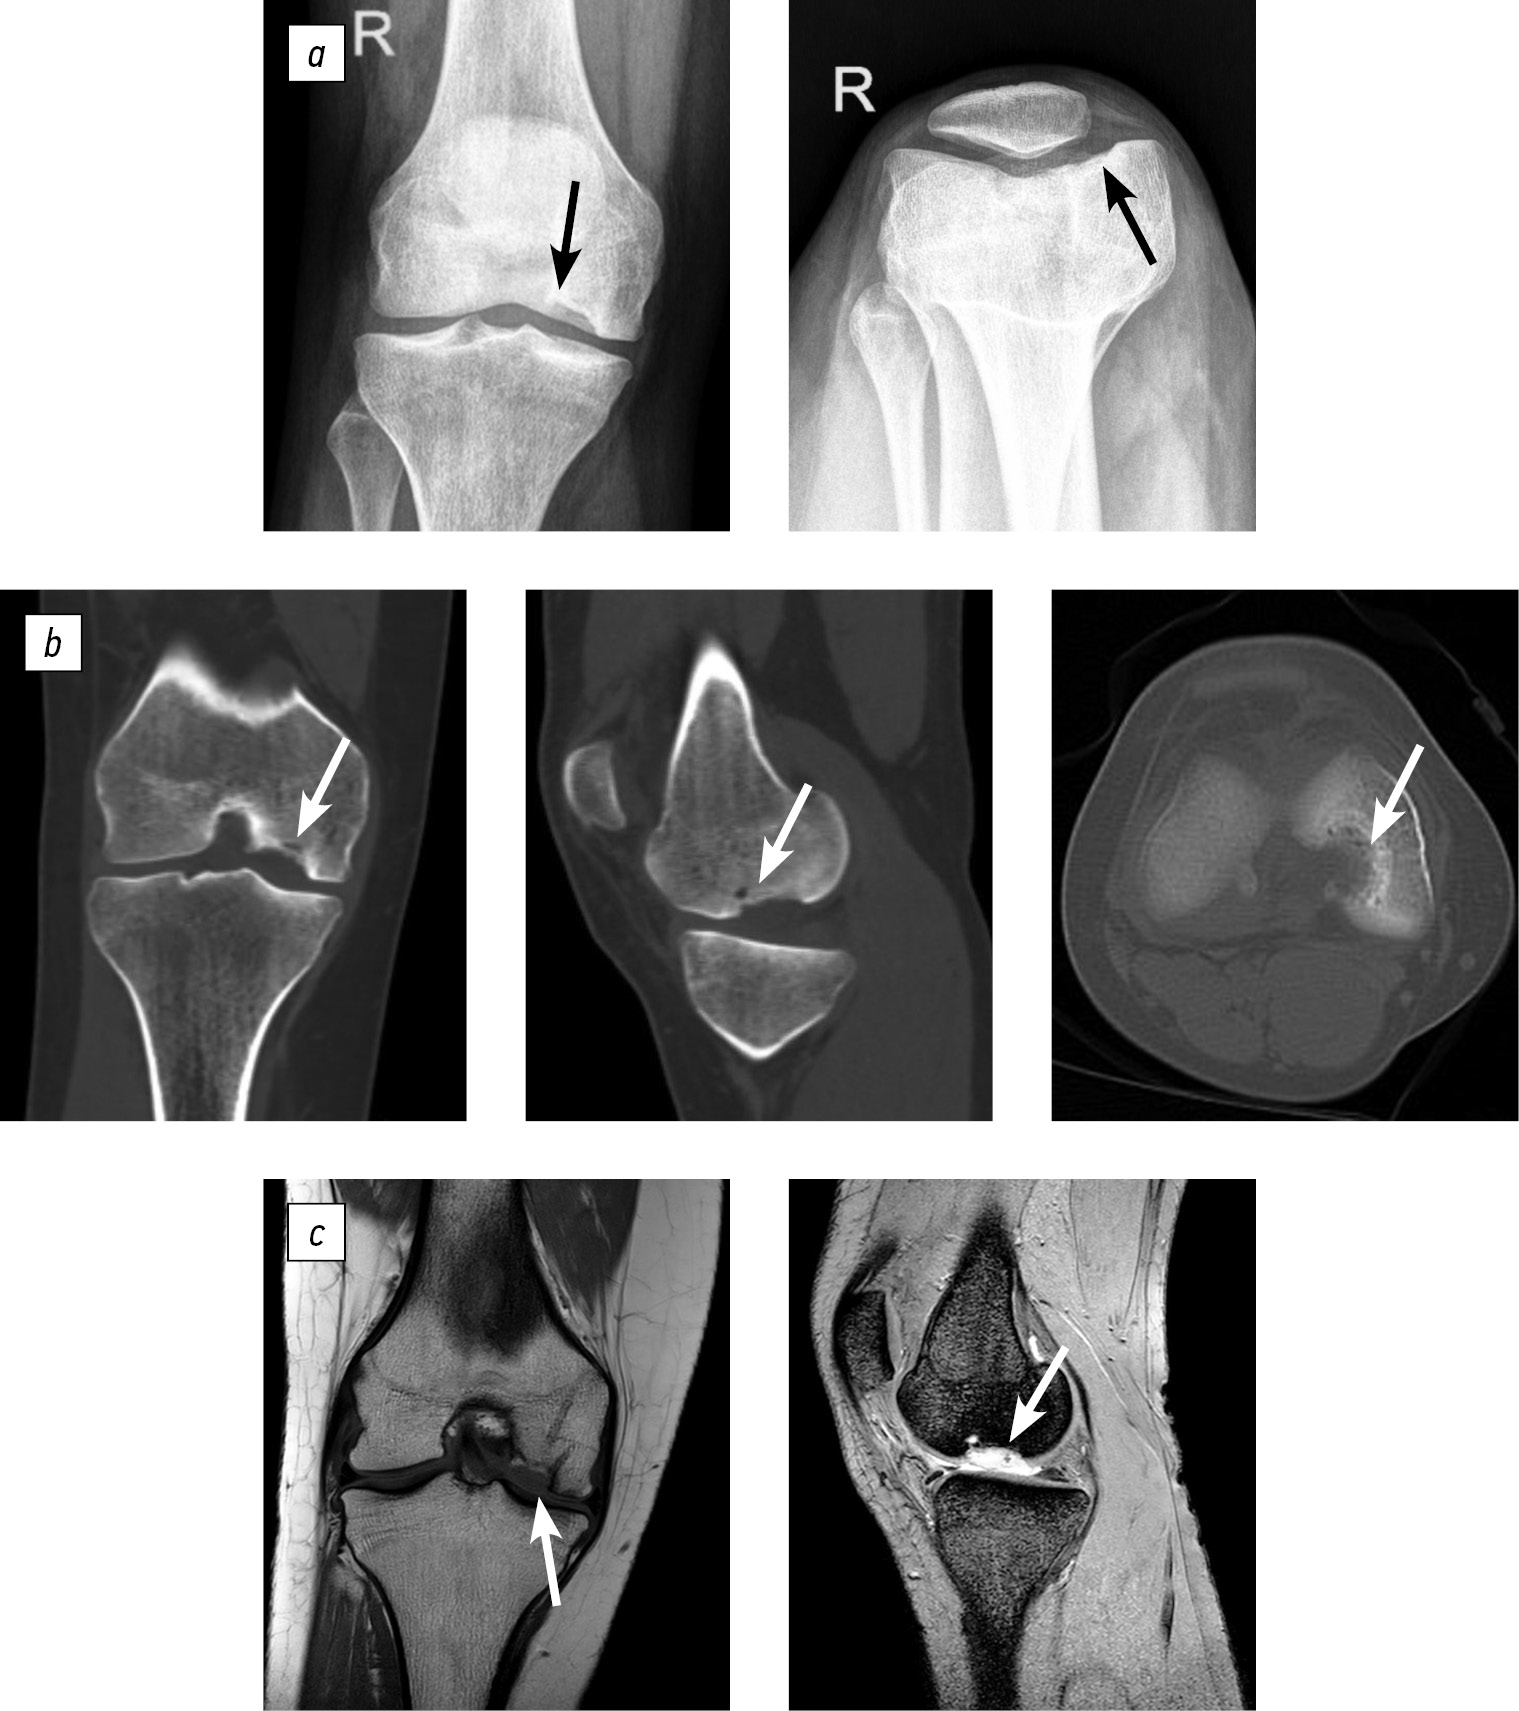

Radiographic evaluations—including X-ray, spiral computed tomography, and magnetic resonance imaging—identified an osteochondral defect in the central region of the medial femoral condyle, measuring 2.0 × 1.4 × 1.0 cm. The lesion was classified as a deep defect (ICRS grade IV). Postoperative changes were recorded, accompanied by synovitis of the right knee joint and early signs of secondary deforming osteoarthritis (stages I–II) (Fig. 1).

Fig. 1. Diagnostic imaging of patient B (age: 17 years at admission): a, X-ray of the right knee joint in anteroposterior and axial views; b, computed tomography scans exhibiting frontal, sagittal, and axial slices through the lesion; c, magnetic resonance imaging scans, frontal and sagittal views through the lesion. The area of destruction is indicated by an arrow.

Clinical evaluation was performed 2.5 years after the surgery. The patient reported no active complaints. She experienced occasional pain in the right knee joint after prolonged walking (for more than 2–3 km). The range of motion in the knee was full and painless. Functional scores: Lysholm, 92 points; KSS, 95 points (Fig. 4).

Fig. 4. Follow-up clinical and imaging evaluation of patient B at 2.5 years after reconstruction: a, range of motion in the right knee joint; b, magnetic resonance images in the frontal and sagittal planes.

Imaging examinations revealed an osteochondral destruction zone in the lateral condyle of the left femur measuring 3.3 × 2.8 × 1.5 cm, along with a loose osteochondral body measuring 2.2 × 2 × 0.5 cm (ICRS grade IV). The imaging findings are shown in Figure 5.

Fig. 5. Imaging of patient M.: a, magnetic resonance imaging, sagittal slice; b, spiral computed tomography, sagittal slice through the osteochondral defect of the lateral femoral condyle; c, spiral computed tomography, 3D reconstruction illustrating the size of the defect and the presence of a loose osteochondral fragment in the lateral femoral condyle. Arrows indicate the osteochondral defect region and the loose osteochondral fragment.

Follow-up computed tomography revealed full consolidation and integration of the bone graft (Fig. 7).

Fig. 7. Patient M. Computed tomography of the left knee joint with three standard projections. The bone graft zone is indicated by an arrow.